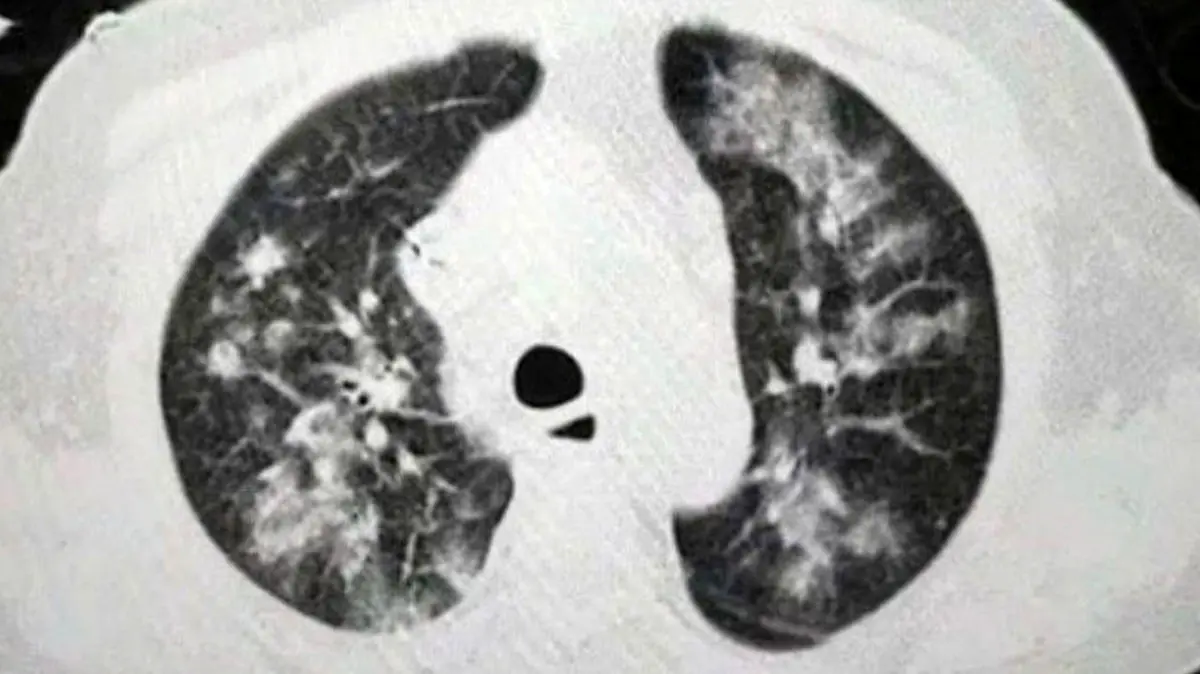

سرطان ریه بنا به تحقیقات کارشناسان بواسطه استفاده طولانی مدت از ماسک گسترش می یابد.

به گزارش رکنا، مطالعه اخیر در مجله "Cancer Discovery" نشان داد که استنشاق میکروب‌های مضر می‌تواند در مرحله پیشرفته سرطان ریه در بزرگسالان نقش داشته باشد و استفاده طولانی‌مدت از ماسک ممکن است به تولید این عوامل بیماری‌زای خطرناک کمک کند.

پایگاه اطلاعاتی "گلوبال ریسرچ" در این‌ باره نوشت میکروب‌شناسان اتفاق‌نظر دارند که استفاده مکرر از ماسک باعث ایجاد یک محیط مرطوب می‌شود که در آن میکروب‌ها اجازه رشد و تکثیر قبل از ورود به ریه‌ها را دارند؛ این دسته از میکروب‌های خارجی سپس از نای عبور کرده و به داخل دو لوله به نام "برونش" حرکت می‌کنند تا به کیسه‌های هوای کوچک پوشیده شده از رگ‌های خونی به نام "آلوئول" برسند.

طبق این مطالعه، این میکروب‌ها پس از حمله به ریه‌ها باعث ایجاد پاسخ التهابی در پروتئین‌های معروف به "سیتوکین IL-17" در ریه می‌شوند.

تیم تحقیق با بررسی میکروب‌های ریه یک مرد 83 ساله که به سرطان ریه مبتلا بود، کشف کرد که کلونی‌ باکتری‌های "ویلونلا"، "پرووتلا" و "استرپتوکوکوس" که ممکن است از طریق پوشیدن ماسک به مدت طولانی پرورش داده شوند، در بیماران مبتلا به سرطان ریه به مقدار بیشتری یافت می‌شود.

علاوه بر این، تحقیقات در مورد پرورش باکتری‌های "ویلونلا" در ریه‌های موش‌ها نشان داد که وجود چنین باکتری‌هایی منجر به ظهور سلول‌های سرکوب‌کننده سیستم ایمنی و همچنین سلول‌های التهابی مانند "سیتوکین IL-17" می‌شود.